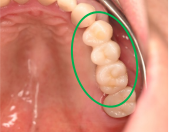

Before

※赤丸は、歯根が破折していたため抜歯しました

※黄色丸は、2006年10月に埋入したインプラント

After

※緑丸は、今回埋入したインプラント